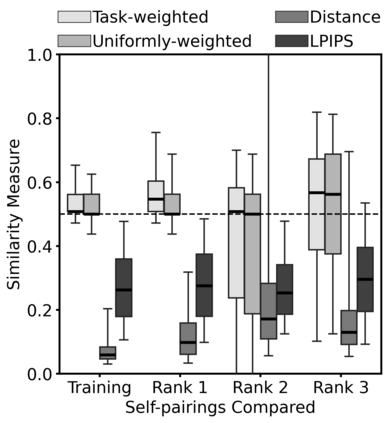

Super-resolution, in-painting, whole-image generation, unpaired style-transfer, and network-constrained image reconstruction each include an aspect of machine-learned image synthesis where the actual ground truth is not known at time of use. It is generally difficult to quantitatively and authoritatively evaluate the quality of synthetic images; however, in mission-critical biomedical scenarios robust evaluation is paramount. In this work, all practical image-to-image comparisons really are relative qualifications, not absolute difference quantifications; and, therefore, meaningful evaluation of generated image quality can be accomplished using the Tversky Index, which is a well-established measure for assessing perceptual similarity. This evaluation procedure is developed and then demonstrated using multiple image data sets, both real and simulated. The main result is that when the subjectivity and intrinsic deficiencies of any feature-encoding choice are put upfront, Tversky's method leads to intuitive results, whereas traditional methods based on summarizing distances in deep feature spaces do not.